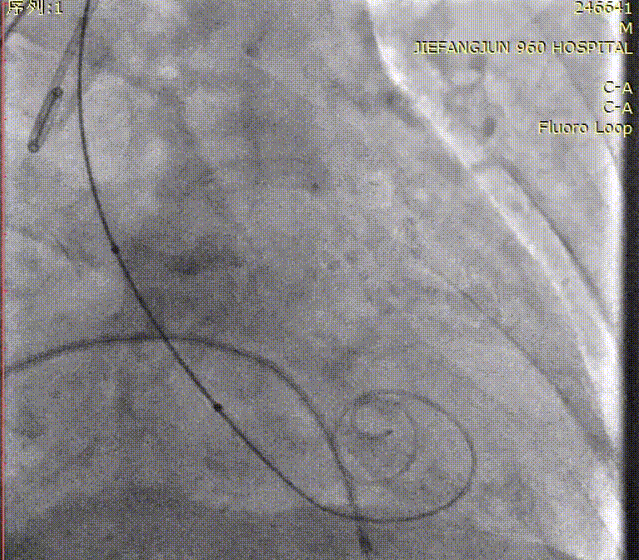

随后,沿加硬导丝送入体外预装好的Prizvalve® THV 23瓣膜,顺利过弓跨瓣,精准定位后,以180次/分快速起搏,待收缩压降到50mmHg时,2-8定位、减容策略进行释放瓣膜。

瓣膜定位造影

瓣膜释放后造影